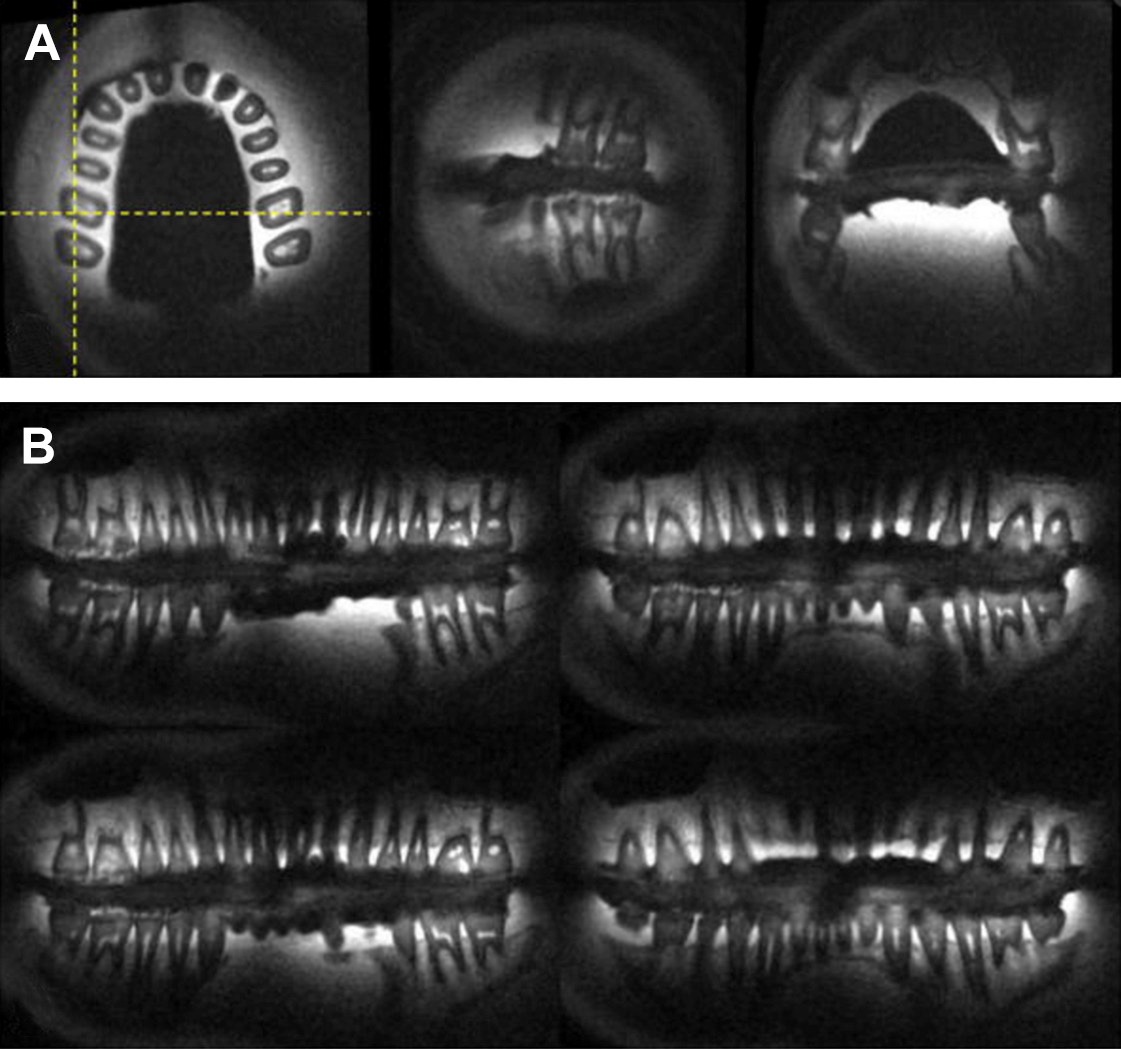

Magnetic Resonance Imaging (MRI) in dentistry is a non-invasive imaging technique that uses strong magnetic fields and radio waves to produce detailed images of oral and maxillofacial soft tissues. Unlike X-rays or CT scans, MRI does not use ionizing radiation, making it a safer option for repeated imaging. In dentistry, MRI is especially useful for evaluating temporomandibular joint (TMJ) disorders, salivary gland diseases, soft tissue tumors, cysts, and infections. It provides excellent contrast between different soft tissues, allowing precise assessment of muscles, nerves, blood vessels, and cartilage. Although MRI is limited in visualizing hard tissues like teeth and bone, ongoing technological advancements are expanding its applications. Overall, MRI serves as a valuable complementary diagnostic tool in modern dental practice. dental clinic in Nolambur, dentist in Nolambur, best dental clinic in Nolambur, best dentist in Nolambur, root canal treatment in Nolambur, dental crowns and bridges in Nolambur, wisdom tooth removal in Nolambur, dental brackets and wires in Nolambur, denture treatment in Nolambur, near me , dental clinic in Mogappair, dentist in Mogappair, best dental clinic in Mogappair, best dentist in Mogappair, root canal treatment in Mogappair, dental crowns and bridges in Mogappair, wisdom tooth removal in Mogappair, dental brackets and wires in Mogappair, denture treatment in Mogappair, near me.